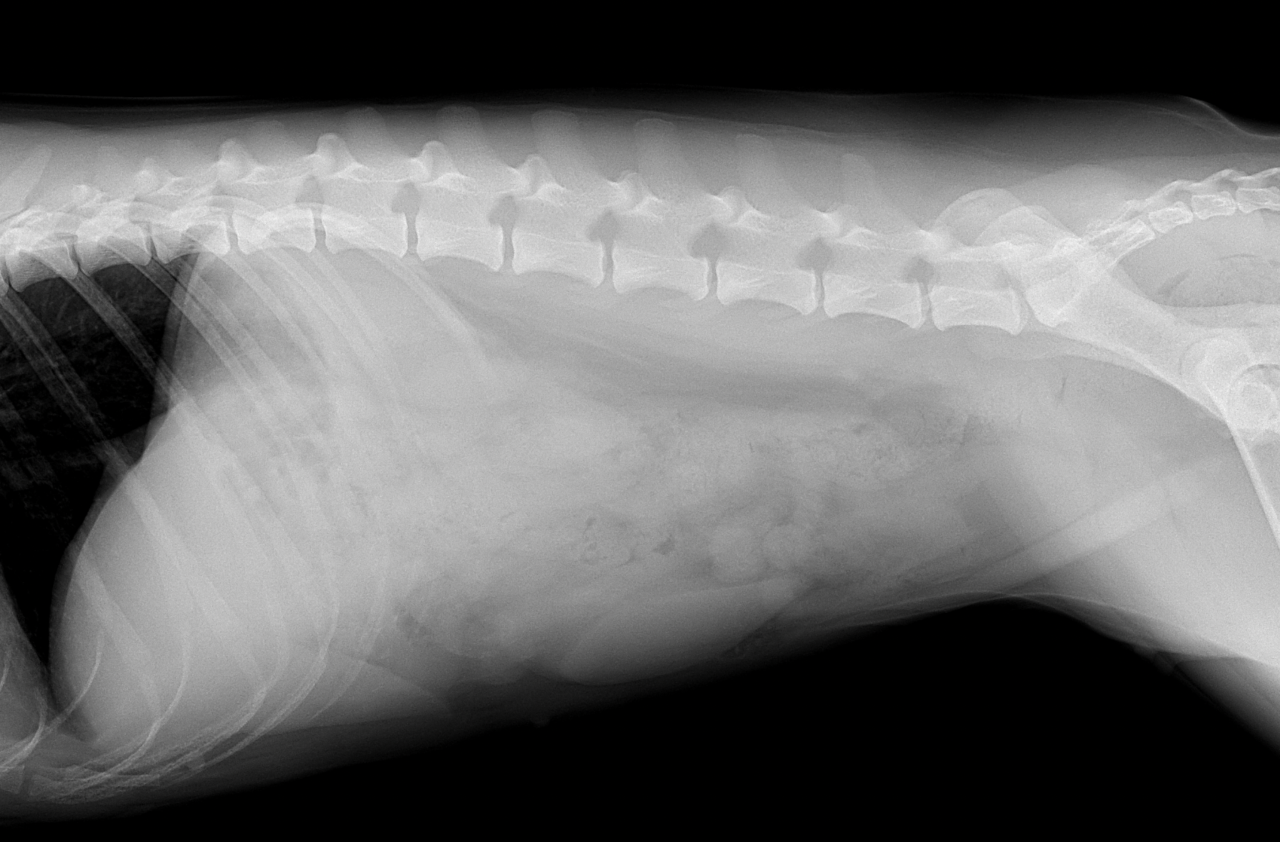

1週間前に団子を串ごと誤飲した可能性があるワンコが急にぐったりしているとのこと。すぐに地元の救急病院を受診すると異物による胃穿孔が疑われました。外科的な摘出と腹膜炎によるクリティカルケアが予想されたため紹介来院しました。開腹後、竹串による胃穿孔が確定されました。腹膜炎も同時に起こっています。穿孔創を封鎖し、腹腔洗浄とドレインの設置を行いました。幸いにも48時間後に食欲が出て退院となりました。愛犬が竹串を誤飲してしまったら、命に関わる事態に発展する可能性もあるため、早めに内視鏡による摘出をお勧めします。このような異物を発見するためにはエックス線よりも超音波検査が非常に有効です。